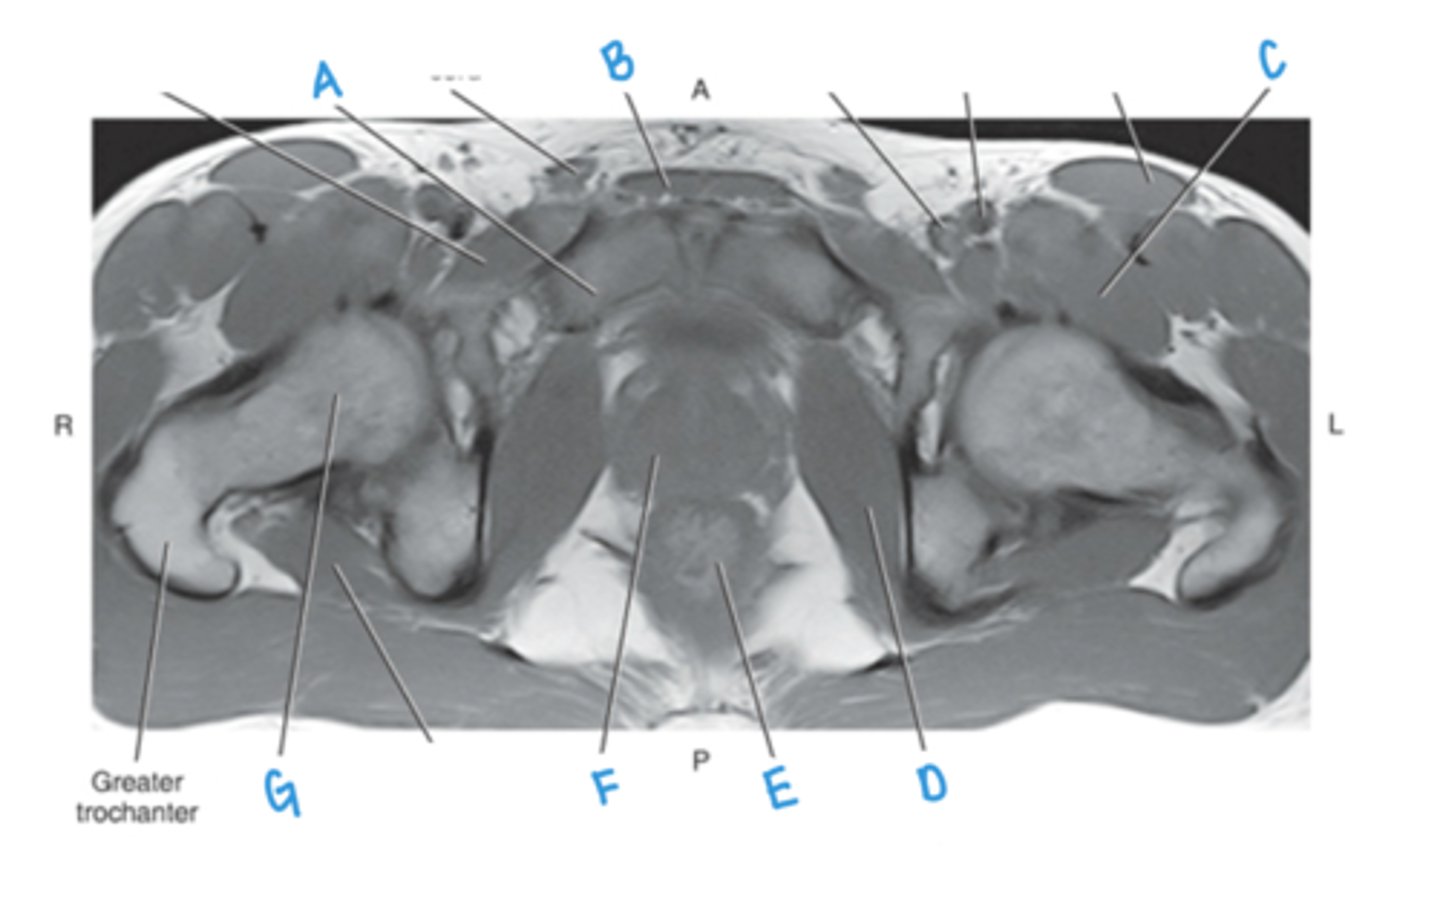

ilium

A

prostate

B

obturator internus muscle

C

ischium

D

rectum

E

levator ani muscle (pubic diaphragm)

F

seminal vesicles

G

bladder

H